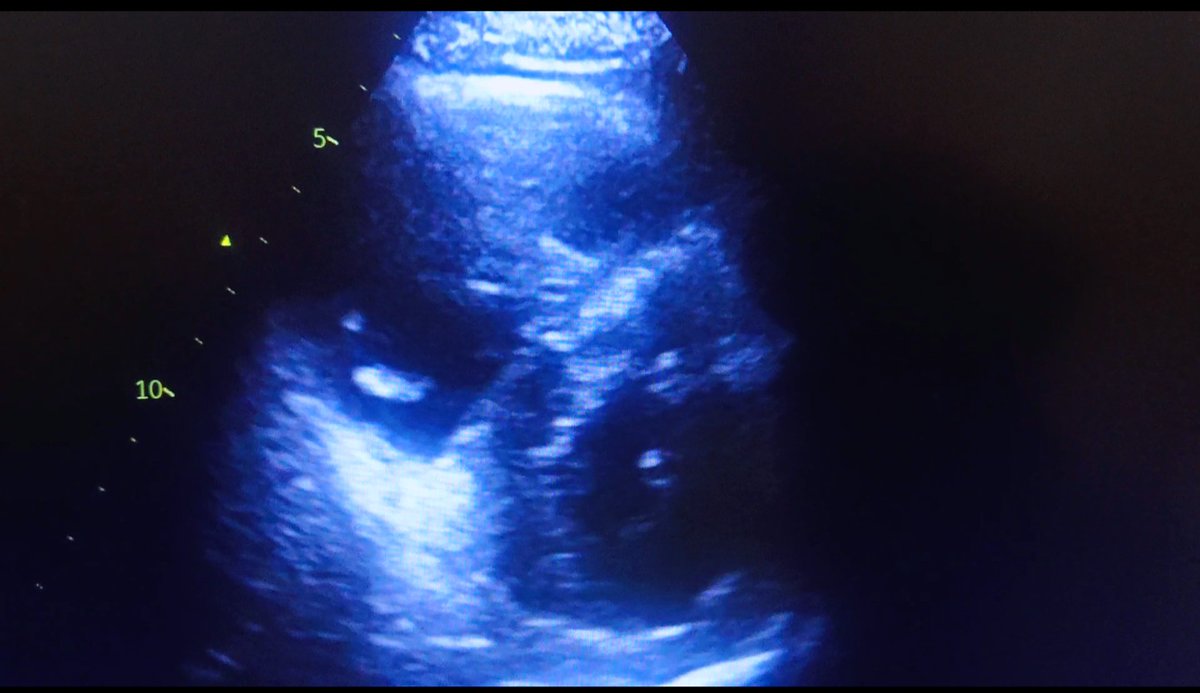

H de 50 ans,

Détresse respiratoire aigue

A l'écho:

- cœur pulmonaire aigu/HTAP, avec un thrombus au niveau de l'artère pulmonaire, et probable thrombus intra VD.

-> Thrombolyse par de l'alteplase.

-> admission en USIC.